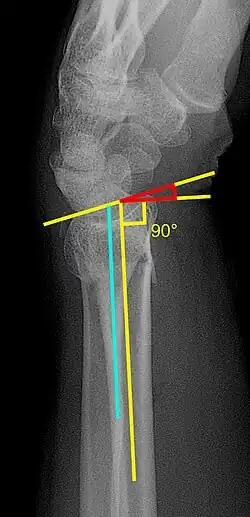

Descendiente de una familia turco-griega afincada en París, finalizó sus estudios en 1960, y tras unos primeros años dedicado a la cirugía general se especializó en cirugía ortopédica. Asimismo se destacó por el desarrollo de nuevos procedimientos diagnósticos y terapéuticos, como la prótesis “cardan”[2] o el método de tratamiento de fracturas de muñeca.[3]